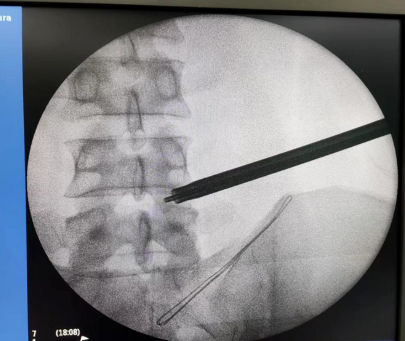

手术经过:术前仔细阅片,精确定位手术靶点部位、规划手术路径、测量通道长度、头尾倾角度。C臂透视定位、局部麻醉、穿刺建立通道、环锯进行关节突成形,连接椎间孔镜系统、椎间盘摘除、神经根管探查减压、侧隐窝减压、彻底检查无卡压后关闭伤口。手术成功,患者术后3天康复出院。

术中穿刺及关节突成形

建立工作通道